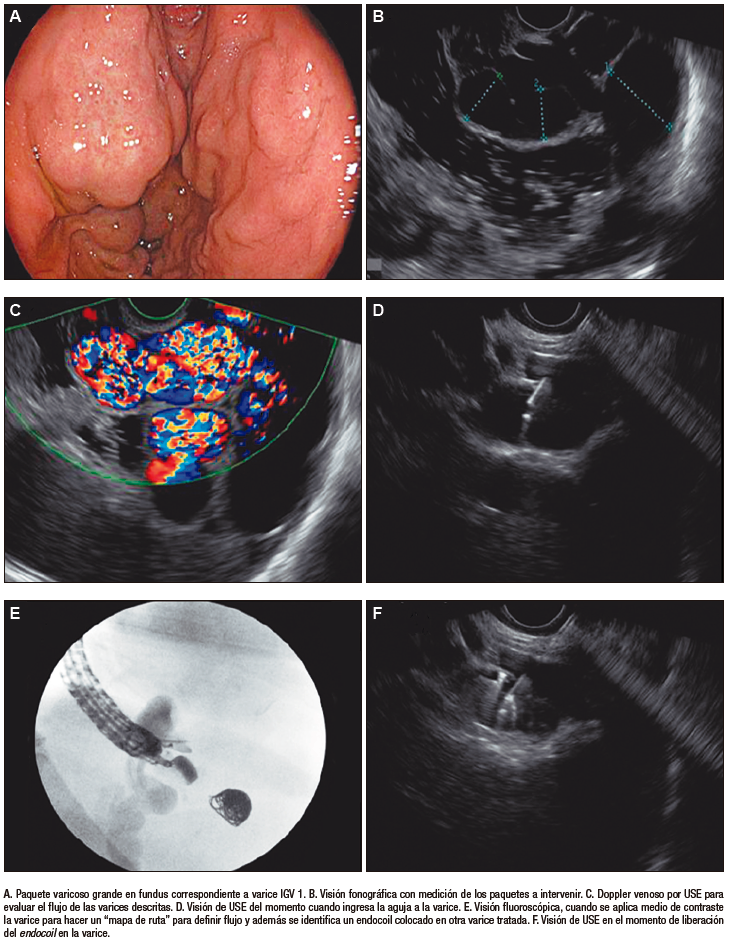

El vaso responsable se identificó mediante la presencia de sangrado activo o hallazgos endoscópicos de alto riesgo. El tamaño de la várice y la permeabilidad se confirmaron mediante la evaluación sonográfica y el examen doppler. Se aplicó en todos los casos agua en el fundus gástrico para mejorar la ventana acústica y definir mejor las estructuras vasculares, se realizó la evaluación de los vasos y la búsqueda del vaso nutricio del paquete varicoso a intervenir. Luego, desde la posición transcrural, se puncionó la várice responsable con una aguja de 19G y se administró una pequeña cantidad de medio de contraste yodado para delinear mejor el vaso, dibujar un «mapa de ruta» vascular y evaluar la presencia de shunts vasculares. Después se desplegaron los endocoils Interlock de Boston Scientific® de tamaños entre 10, 12, 15 mm de diámetro por 20 a 40 cm de longitud (esta medida se definió según el tamaño de la várice a tratar). Se realizó dicha inserción bajo control endosonográfico y fluoroscópico de forma simultánea. Al finalizar el despliegue, se realizó un control endosonográfico con doppler sobre el vaso responsable, con el fin de confirmar la obliteración de la várice (Figura 1). En los casos donde continuaba con un flujo importante mediante el Doppler, o con una circulación significativa, se procedía a aplicar otro endocoil o cianoacrilato guiado por USE.

Figura 1. Descripción del paso a paso de la técnica de inserción de endocoils guiado por ultrasonido endoscópico